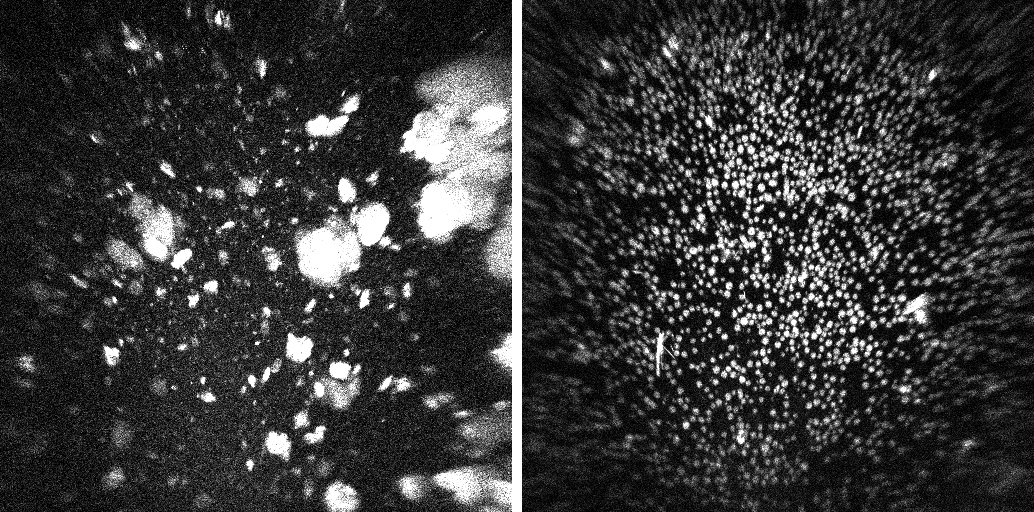

UV imaging of a ground control sample (left) and spaceflight sample (right) from Merck’s research shows the much more uniform size and distribution of crystals grown in microgravity. These results helped researchers to refine ground-based production of uniform crystalline suspensions required for an injectable version of KEYTRUDA.Merck Since 2014, Merck has flown crystal growth experiments to the space station to better understand how crystals form, including the monoclonal antibody used in this cancer treatment. Monoclonal antibodies are lab-made proteins that help the body fight diseases. This research focused on producing crystalline suspensions that dissolve easily in liquid, making it possible to deliver the medication by injection. In microgravity, the absence of gravity’s physical forces allows scientists to grow larger, more uniform, and higher-quality crystals than those grown in ground-based labs, advancing medication development and structural modeling.